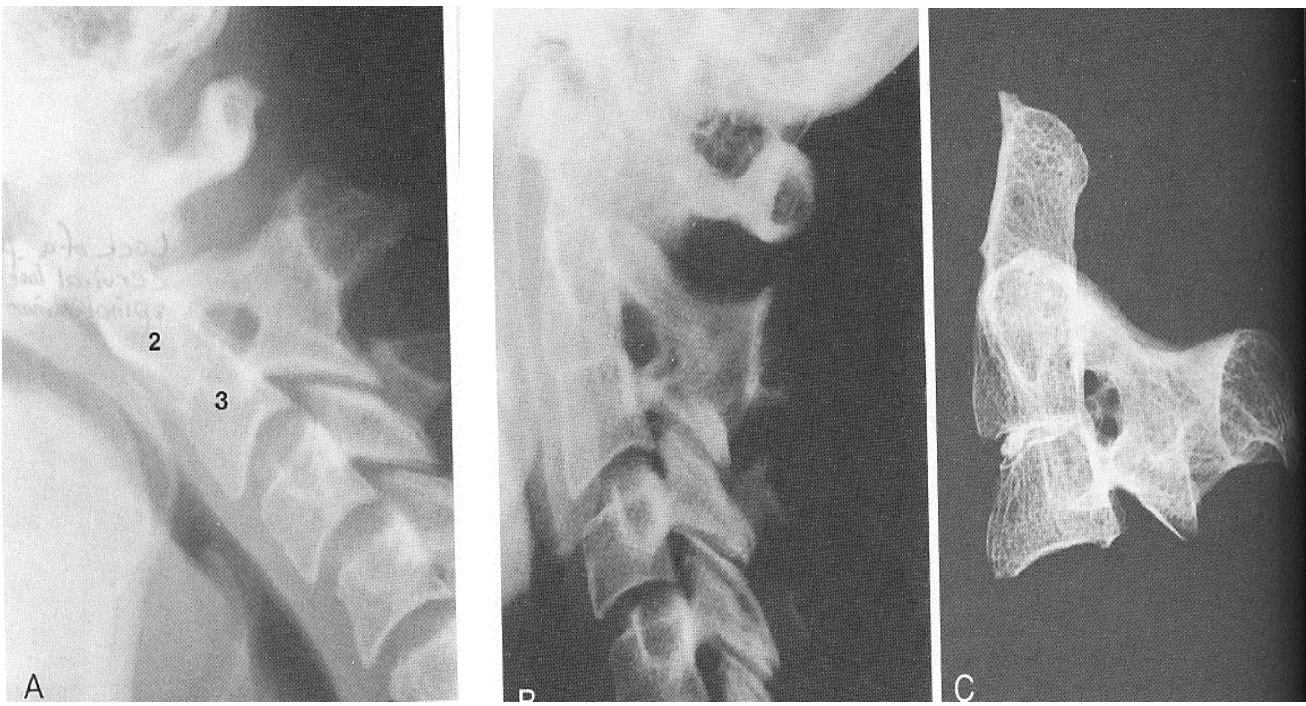

What is this deformity called? -congenital elevation of the scapula -scapula and potentially clavicle fail to descend

sprengel's deformity

In sprengel's deformity, where does the scapula remain?

C4/C5 where it embryonically developed

Is sprengel's deformity usually unilateral or bilateral?

unilateral

A patient with sprengel's deformity will have decreased....

abduction of the arm and torticollis

What is sprengel's deformity associated with?

Lippel-Feil syndrome in 25% of cases and omovertebral bone in 40% of cases

What is an omovertebral bone?

bony bridge between C5/C6 SP, lamina, or TP to the superior angle of the scapula

What has these radiographic features? -scapula shortened vertically -inferior angle above normal at T7 level

What is this?